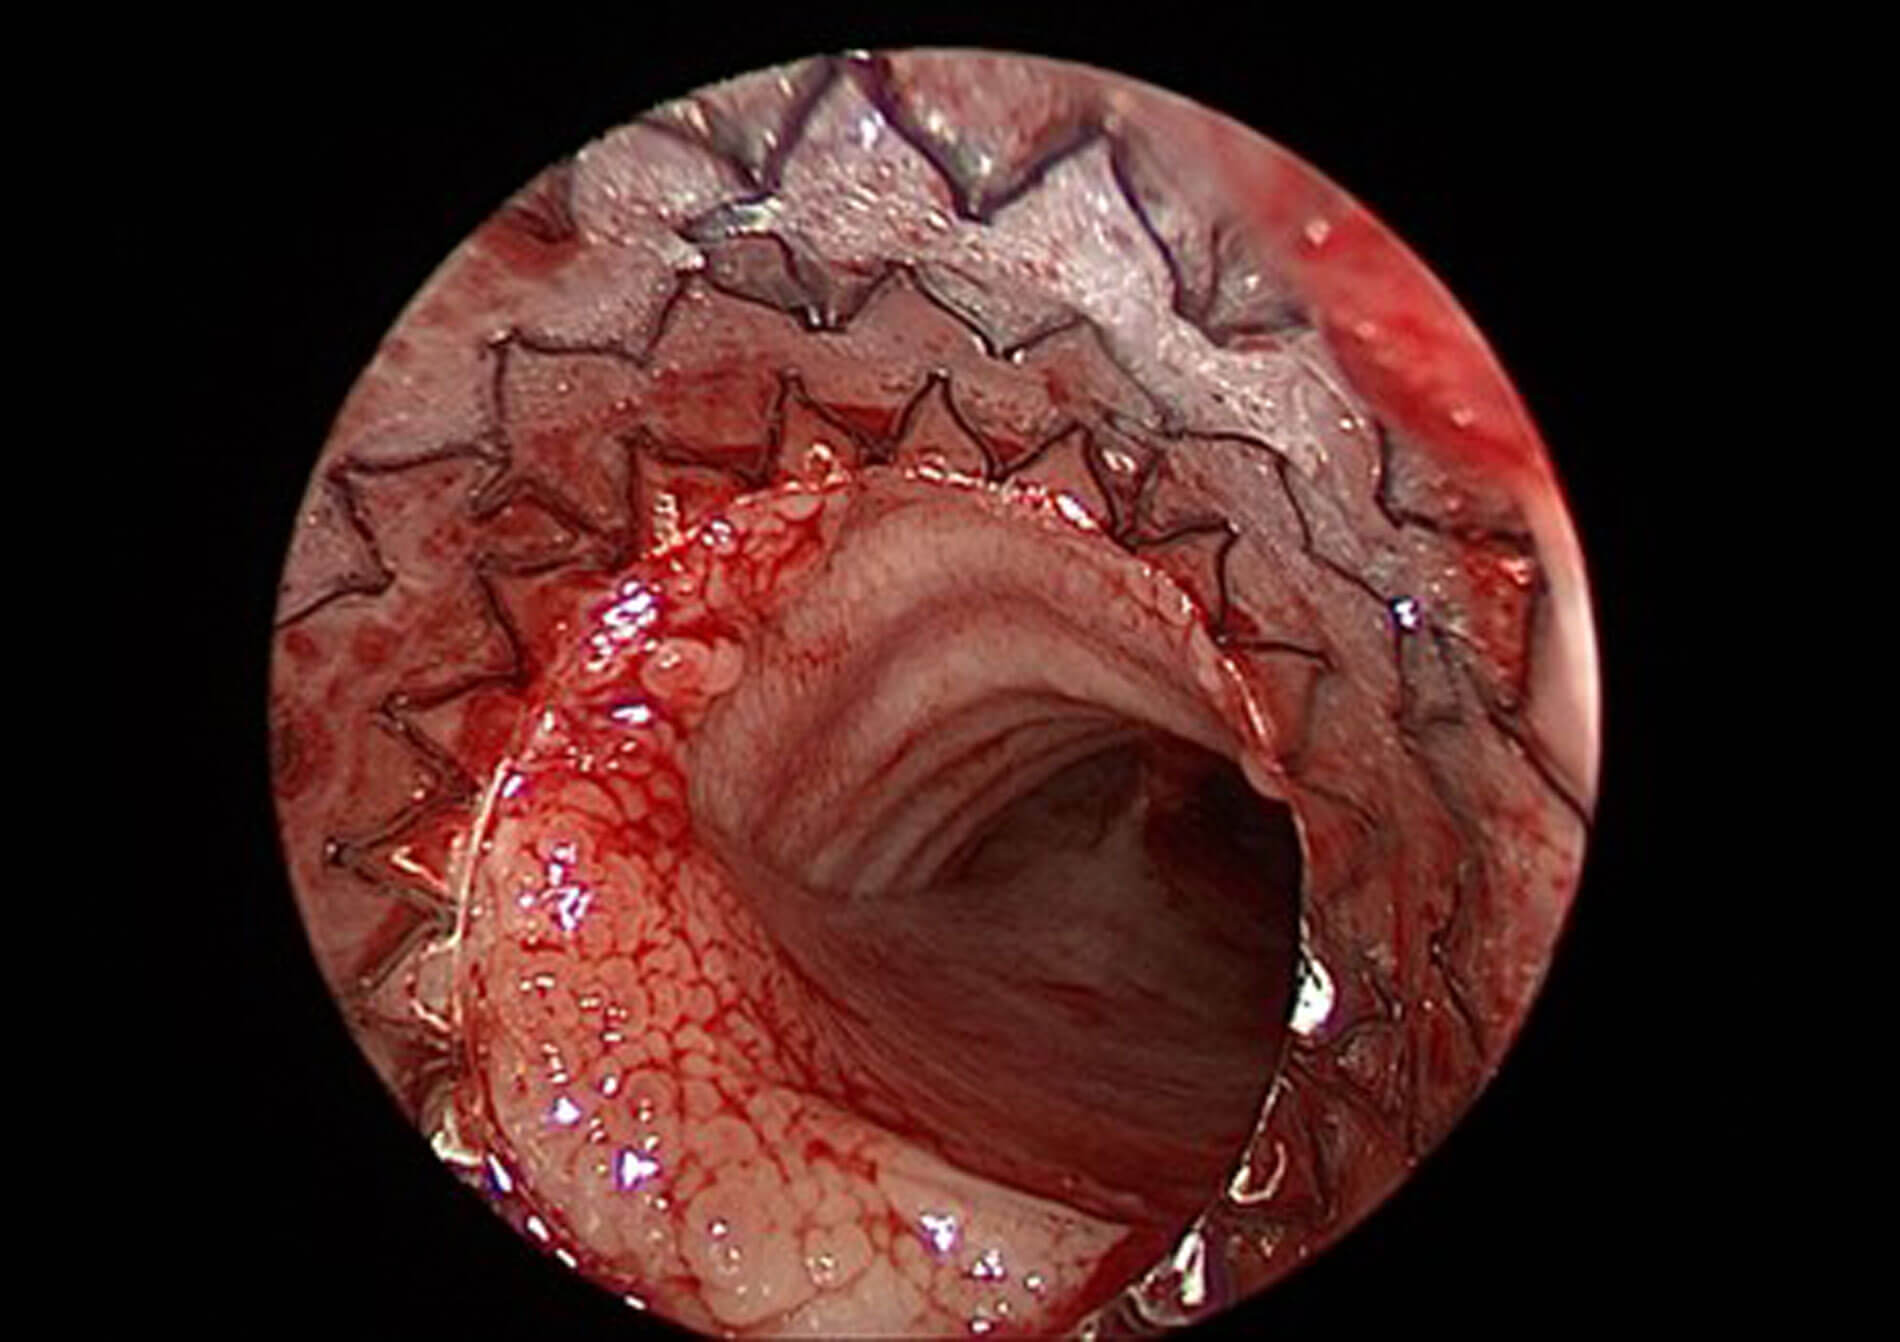

In the operating theatre, technology is also transforming the way we work. Two promising technologies are on the rise, and are popular in congress talks: artificial intelligence (AI) and robotics. Although they can greatly improve healthcare, they also bring important ethical issues as they tend to add in interface between the patient and the surgeon, risking a ‘dehumanisation’ of patient care. They can also add considerable technicality to an otherwise straightforward surgical procedure and require the help of medical engineers. For example, robotics and AI may render automated cochlear implantation possible in the next 10 years which could be a fantastic advance for safer, faster and minimally invasive procedures in patients. The future generation of surgeons may have to reinvent their trade, becoming risk assessors and procedure managers, rather than operators with a direct contact with the patient.